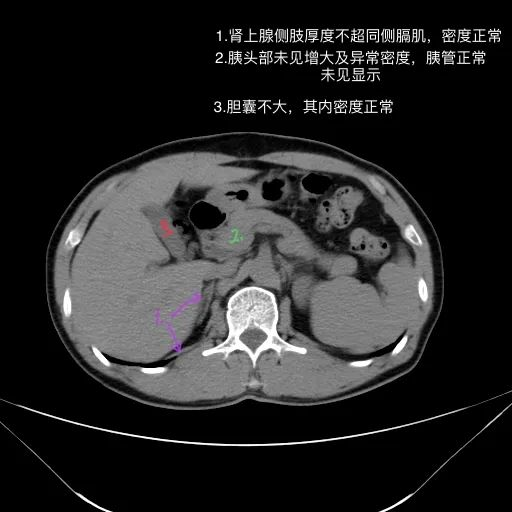

肝脏缩小,包膜凹凸不平,肝裂增宽,各叶比例失衡,肝实质密度不均,肝S4小片低密度影,约cm;胆囊不大,其内未见异常密度影,胆道系统未见扩张;胰腺、脾脏形态、密度、大小未见异常;双肾上腺及双肾形态、密度、大小未见异常,双输尿管未见扩张,膀胱充盈良好,壁光滑,其内未见异常密度影;前列腺未见异常;胃肠道未见充盈,壁未见明确增厚,食管胃底多发迂曲、增粗血管,腹部及腹膜后未见肿大淋巴结;腹水。

1.肝硬化失代偿表现(腹水,食管胃底静脉曲张)。

2.肝S4小片低密度影,建议复查或进一步检查。